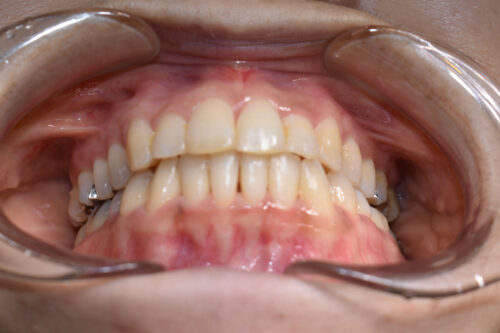

ワイヤー矯正治療9か月後です。

本症例も

上顎左右臼歯部に

歯科矯正用アンカースクリュー(デュアル・トップオートスクリュー)を用い

下あごを オートローテーションさせ

また 上下の歯列全体を

後方へ移動させることで

歯を抜かなくても

口元の改善も行いました。

上下の正中には 若干ずれが残存しましたが、

かみ合わせ重視で

終了いたしました。